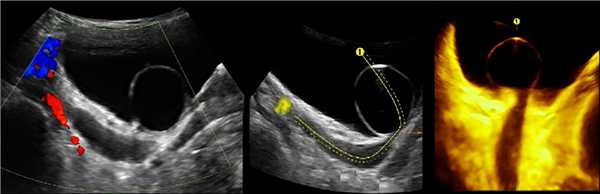

На УЗИ в мочевом пузыре или в уретре определяется анэхогенное образование, округлой формы, с четким и ровным контуром; соответствующий мочеточник обычно заметно расширен; может присутствовать гидронефроз верхней части удвоенной почки. Уретероцеле определяют как внутрипузырные (полностью внутри мочевого пузыря) или внепузырные (некоторая часть постоянно расположена в шейке мочевого пузыря или в уретре).

Рисунок. Двустороннее уретероцеле на УЗИ: в режиме ЦДК из верхушек уретероцеле определяется выброс мочи.

Рисунок. На УЗИ в уретероцеле определяется гиперэхогенная структура с акустической тенью — камень. Уретероцеле может являться одним из факторов, способствующих камнеообразованию.